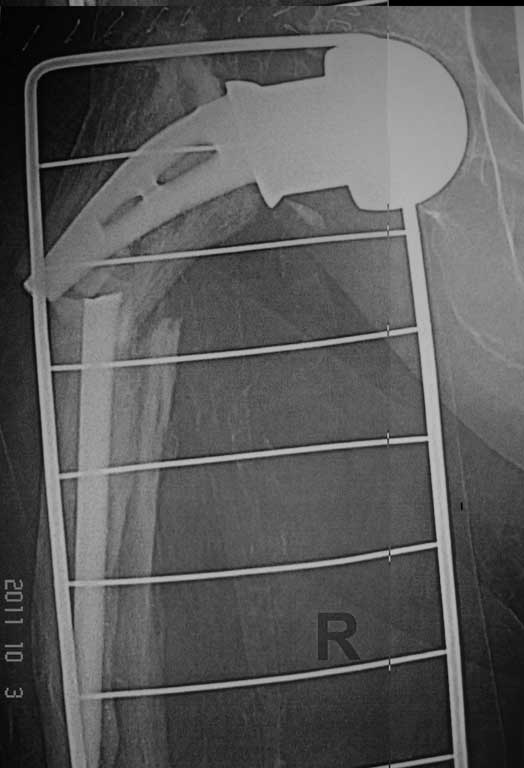

Перипротезный перелом

Добрый вечер. Уважаемые коллеги, впервые столкнулись с перипротезным переломом правой бедренной кости. Если есть опыт и идеи пожалуйста выскажите по поводу данного случая.

Женщина 86 лет, оперирована нами 6 лет назад по поводу перелома шейки правой бедренной кости . Травма двое суток назад - падение в квартире.Наши мысли по поводу данного случая - удаление протеза сломанной ножки и замена ревизионной цементной ножкой и модульной головкой , при этом не выполнять вскрытие кортикальной стенки в виде окна, для того чтобы убрать остатки цемента ,т.к эта процедура увеличит интраоперационную травму и кровопотерю, а с помощью рашпилей разработать канал, ввести в дистальный отломок цемент и посадить ножку,если будет нужно наложить серкляжные швы.

А были ли симптомы нестабильности протеза до травмы? Падение вряд ли могло быть причиной перелома ножки. По представленному снимку понять, есть ли нестабильность трудно. В любом случае, удаление даже нестабильного протеза без широкого вскрытия ложа может оказаться непреодолимой задачей и расчитывать на то, что это наверняка получится, не стоит. А если один из фрагментов фиксирован стабильно, то и с широким вскрытием канала задача может оказаться не из легких. Другое дело, нужна ли ревизионная ножка если Вы думаете о цементной фиксации? Если не заморачиваться обязательным сращением перелома и подумать о том, чтобы дать пациентке возможность какое то время относительно безболезненно походить с помощью ходунков, то можно поставить любую дешевую цементную ножку, даже из ранее удаленных у других пациентов. Можно и однополюсную.

А Вы это делали при перипротезных переломах, или при переломах ножки протеза, как в данном случае? здесь скорее транспротезный перелом, а не

перипротезный, и возникнуть от мог только при выраженной нестабильности ножки. Поэтому ревизионное протезирование длинной ногой единственно возможный вариант.